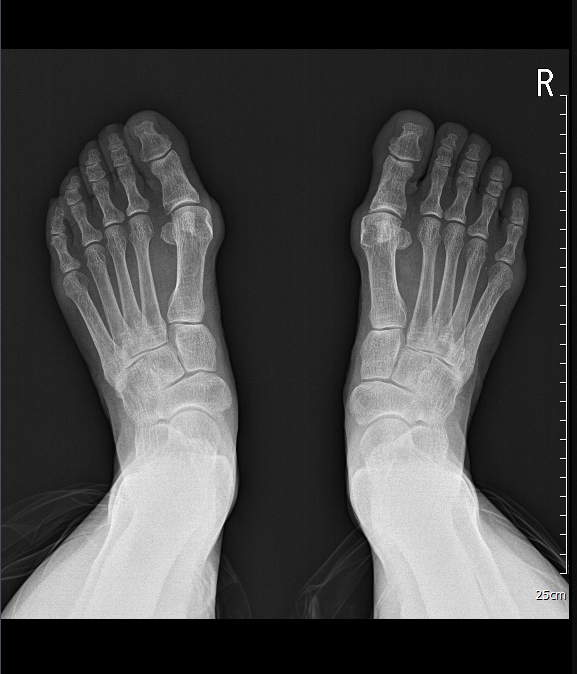

1️⃣ 영상 의학 검사: X-ray를 통해 엄지발가락이 휜 각도(HVA)를 정밀하게 측정합니다.